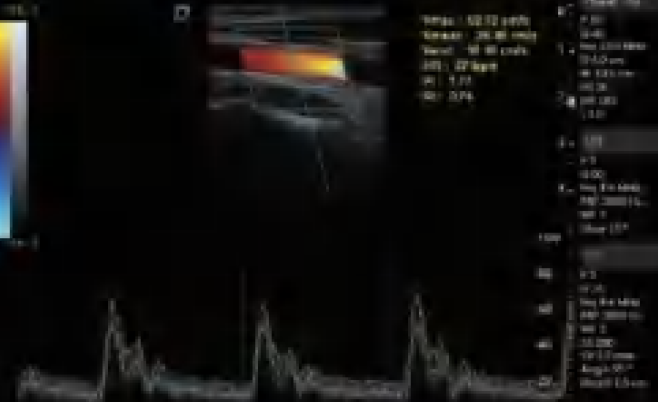

DW-L50 Exp

DW-L50 Exp

Aparato de Diagnóstico Ultrasónico Digital a Color Completo de Tipo Laptop

El DW-L50 Exp, impulsado por la avanzada plataforma de ultrasonido ST-U, ofrece imágenes ultra claras en todo momento. Con una movilidad y adaptabilidad sobresalientes, funciona de manera fiable en diversos entornos clínicos complejos. Su introducción permite que más instituciones médicas accedan a tecnología de ultrasonido rentable y de alto rendimiento.